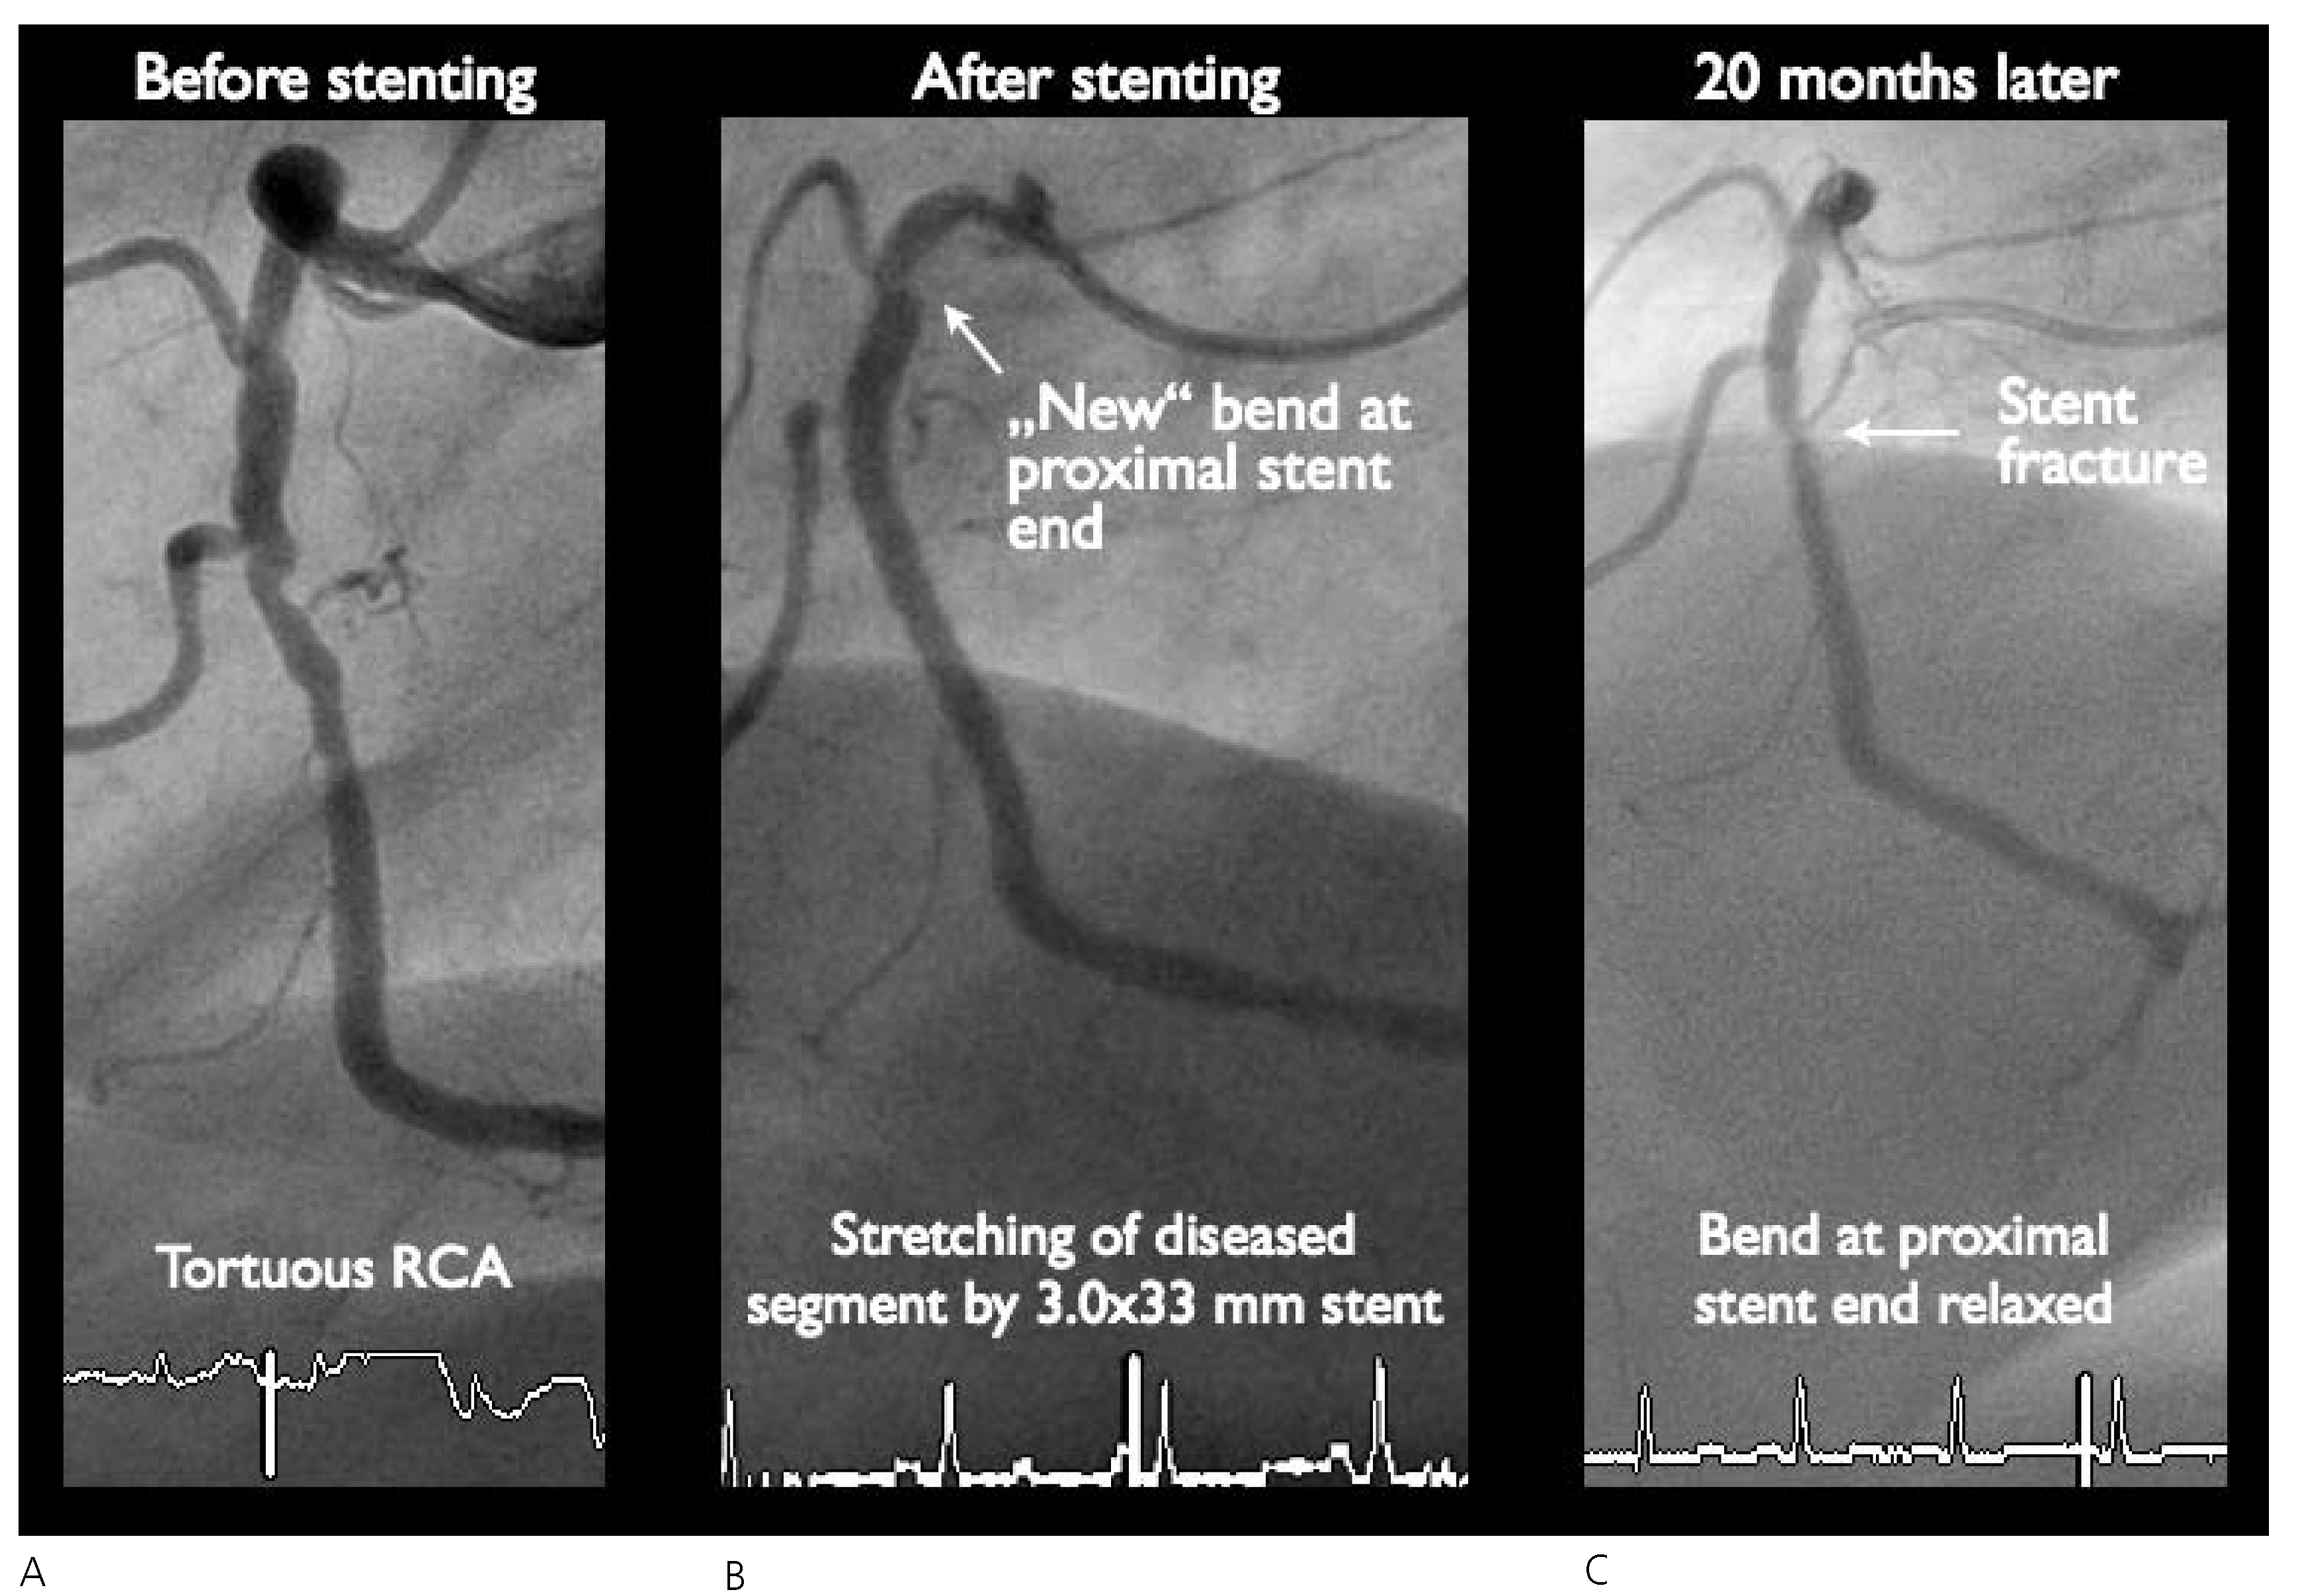

Coronary Stent Fracture: Problem or Blessing?

Case report